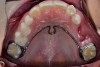

Fig 5. Initial scan for patient needing transpalatal arch to replace first primary molars to be extracted.

Figure 5